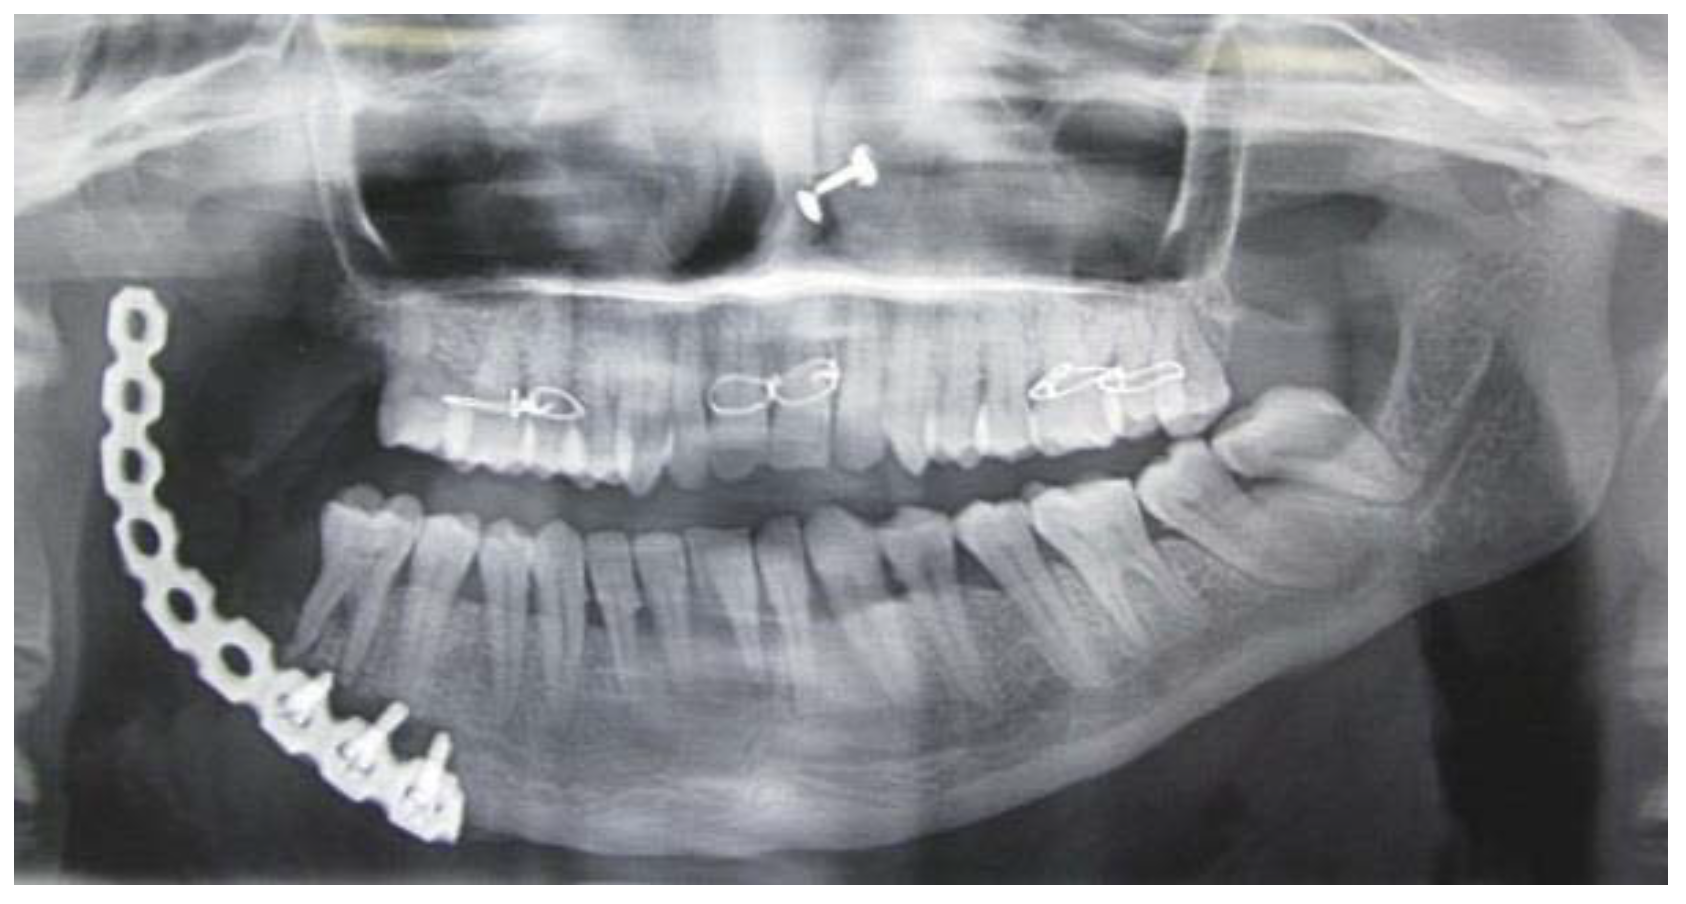

Figure 5.

OPG after segmental mandibulectomy.

Figure 5.

OPG after segmental mandibulectomy.